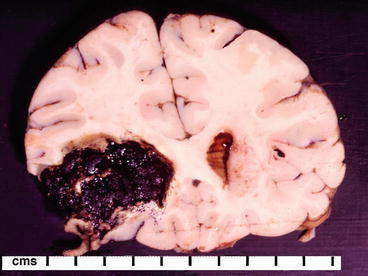

In general, skin changes can include ulcerations, cellulitis, erythema, petechial hemorrhages, purpura, ecchymoses, bullae (both intact and ruptured), and skin desquamation. Typically there is peripheral, dependent, or diffuse edema. On internal examination, pleural, pericardial, and peritoneal effusions may be present. On examination of the organs, there may be little to no abnormal changes, or marked changes resulting from the dissemination of infection, or changes related to hypotension and septic shock. It is not uncommon to see petechiae or hemorrhages on the organ surfaces, particularly the pleura, heart, and thymus. The liver and spleen may be enlarged, softened, and have wrinkled capsules. On sectioning, the spleen may show deliquescence (liquefaction). The liver parenchyma may have accentuation of the lobular architecture, centrilobular hemorrhage, and necrosis. In severe cases of sepsis, there may also be evidence of cholestasis or steatosis. The lungs, heart, liver, spleen, and kidneys may contain infarcts. In the lungs, there may be evidence of edema and congestion, pneumonia, abscess, or diffuse alveolar damage. Diffuse adrenal hemorrhage can be seen in some cases of bacterial sepsis, most notably in association with Neisseria meningitidis sepsis (Fig. 30.1). The kidneys may have scattered infective foci in the cortex with sparing of the medulla indicating hematogenous spread of infection. The heart may be dilated and contain diffuse or localized red-blue lesions or valvular vegetations (Fig. 30.2). The esophagus, stomach, and bowel walls may be thickened, edematous, and congested. There may be bloody material in the intestinal lumen. There may be fat necrosis or hemorrhage in, or surrounding, the pancreas. The brain may have evidence of edema or hemorrhage within the parenchyma (Fig. 30.3).

Fig. 30.3.

Coronal section from the brain of a patient with endocarditis showing an acute parenchymal hemorrhage resulting from a septic embolus in the left middle cerebral artery territory. The hemorrhage extends into the lateral ventricle